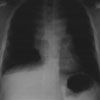

Temperature is 37.3°C (99.1°F); heart rate, 102 beats per minute; respiration rate, 20 breaths per minute; and oxygen saturation on room air, 93%. The head and neck region appear full and erythematous with no visible venous distention. Mild bruising and small distended veins are noted on the right side of the chest wall. Breath sounds are diminished at the right base with wet crackles. No splenomegaly or lymphadenopathy is noted. Anteroposterior and lateral chest radiographs are shown.

The chest radiographs showed a pleural effusion, with blunting of the costophrenic angles (white arrows)-to a greater degree on the right-and a mediastinal mass (yellow arrows). A follow-up CT scan confirmed the presence of a large anterior mediastinal mass that compressed the trachea and surrounding vasculature. Biopsy and flow cytometry of the mediastinal mass established the diagnosis of T-cell lymphoblastic lymphoma.